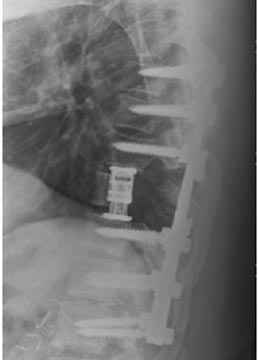

44 year old man with severe low back pain with intermittent radiation of the pain down the right leg. After undergoing conservative treatment, continued to have debilitating pain. MRI revealed a right paracentral disc herniation but CT scan revealed a unilateral pars fracture. After debating on microdiscectomy vs fusion, patient elected to undergo lumbar fusion. 4 months postop patient returned to surfing again. 9 months postop patient wrote “My recovery continues to do very well and we just got back from 8 days camping which including mountain biking, hiking, and a lot of work. Surfing almost every day and life is good…you have helped get my life and my families life back to normal.”

After procedure.